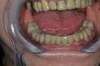

RÉHABILITATION TOTALE MANDIBULAIRE SUITE A UN BRUXISME EN PHASE TERMINAL

Une patiente se présente au cabinet avec un délabrement important de sa mandibule.

Les seules propositions qui lui ont été faites sont des avulsions totales et pose d'un appareil complet.

La dimension verticale est à réévaluer ainsi que le calage postérieur.